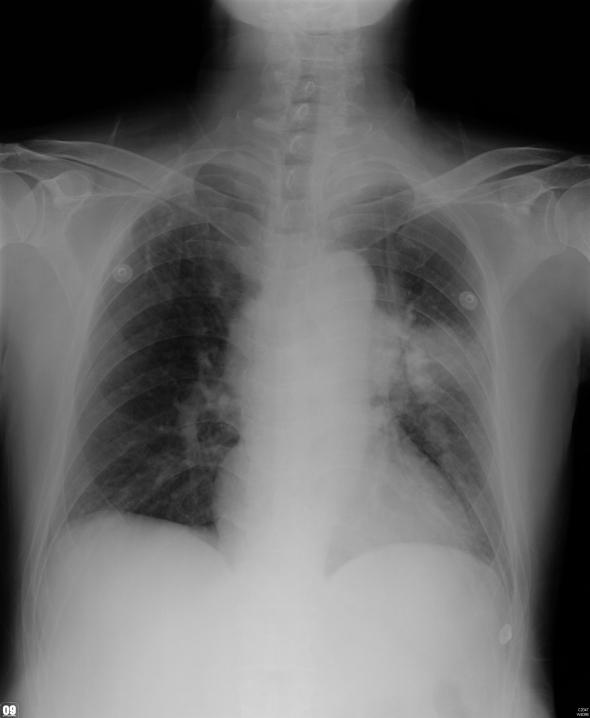

Syncope is a common complaint in clinical medical care. The etiology and mechanism can be complex. We report two cases experienced recurrent syncope to our emergency room without concomitant symptom. The image studies of both cases revealed apical neoplasms compress left common carotid artery with mediastinal lymphadenopathy and without cardiac/main artery trunk involved. After brain lesion, cardiac arrhythmia, and orthostatic hypotension were excluded, syncope related to vagus nerve involved was suspected.

https://cdn.ncbi.nlm.nih.gov/pmc/blobs/984d/3279508/114c6a962700/jocmr-04-77-g001.jpg